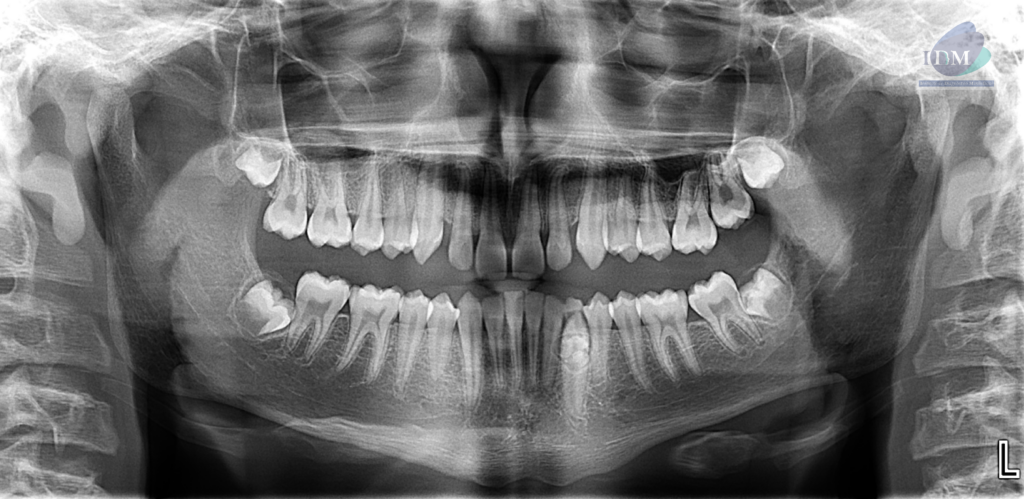

En la radiografía panorámica (Figura 1), se observa imagen de densidad dentaria rodeada de un halo radiolúcido corticalizado proyectado sobre pieza 33. Además de apreciarse la persistencia de pieza 73 y pieza 33 retenida.

Radiografia Panorámica